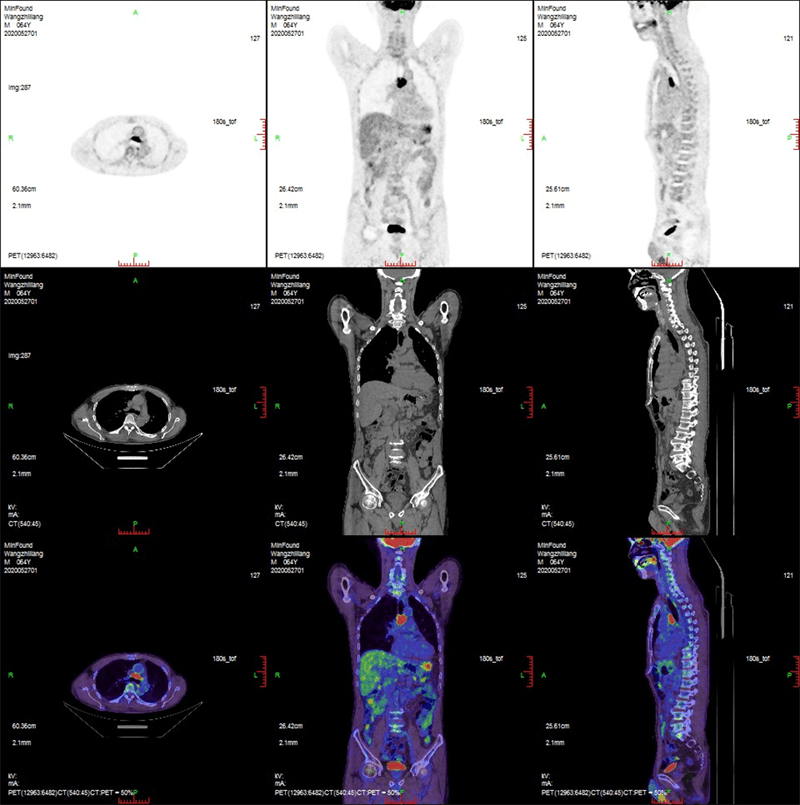

臨床畫廊